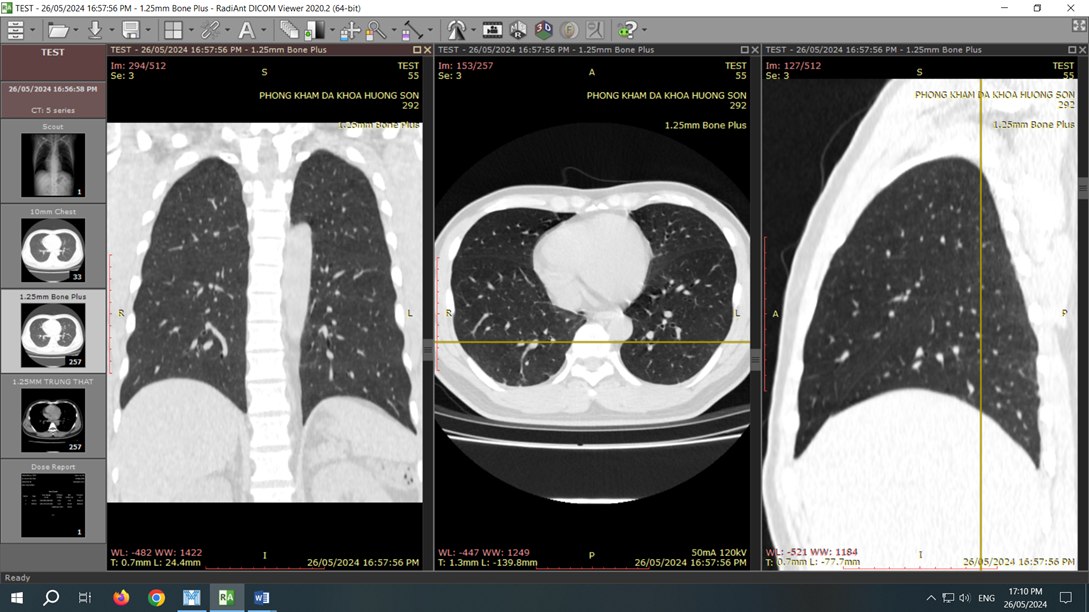

Bệnh nhân M.T.T (50 tuổi, Bình Định) đến phòng khám Hương Sơn tầm soát ung thư định kỳ hàng năm và được chỉ định chụp CT toàn thân với công nghệ CT 2560 lát cắt. Bất ngờ, kết quả chụp CT phát hiện có khối u kích thước khoảng 3cm tại nhu mô gan phải. Kết hợp với kết quả sinh thiết, bác sĩ chẩn đoán xác định bệnh nhân mắc ung thư biểu mô tế bào gan.

“Chụp CT là giải pháp tối ưu phát hiện ung thư sớm, đặc biệt là ung thư gan. Đặc biệt với sự ra đời của công nghệ CT 2560 lát cắt có tích hợp AI và chụp CT quang phổ sẽ giúp phát hiện tổn thương siêu nhỏ, đồng thời cung cấp nhiều thông tin phân tích, định lượng để bác sĩ đánh giá chính xác tổn thương. Như trường hợp của bệnh nhân T rất may mắn khi phát hiện ung thư giai đoạn sớm nên có chỉ định can thiệp nhẹ nhàng, tỉ lệ thành công cao.”

Công nghệ CT 2560 lát cắt cho phép phát hiện các bất thường siêu nhỏ từ 0.23mm, truy vết mầm mống ung thư từ cấp độ tế bào, đảm bảo không bỏ sót bất thường dù là nhỏ nhất.

Sau điều trị ung thư, hệ thống CT 2560 lát cắt là phương tiện hỗ trợ đắc lực, giúp các bác sĩ theo dõi sát diễn biến bệnh và quá trình hồi phục của bệnh nhân. Với ưu thế vượt trội về hình ảnh, CT 2560 lát cắt không chỉ cung cấp hình ảnh 3D sắc nét với độ phân giải cao mà còn giảm nhiễu ảnh hiệu quả nhờ công nghệ CT quang phổ tiên tiến.